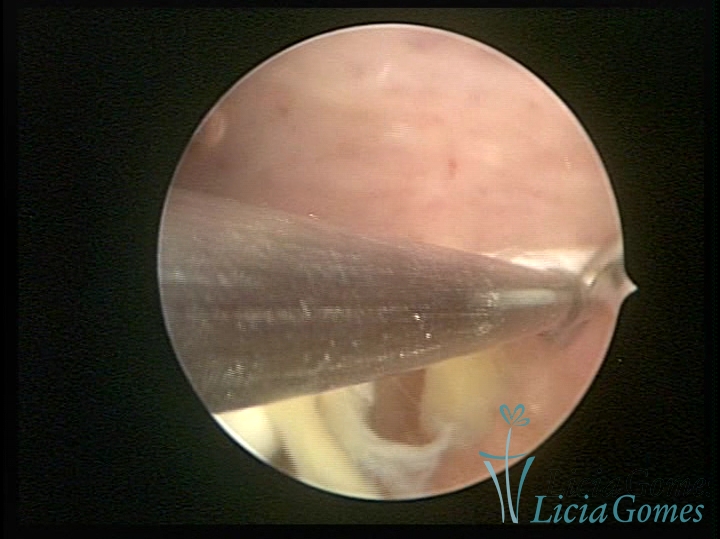

Uterine cavity with an old, folded IUD